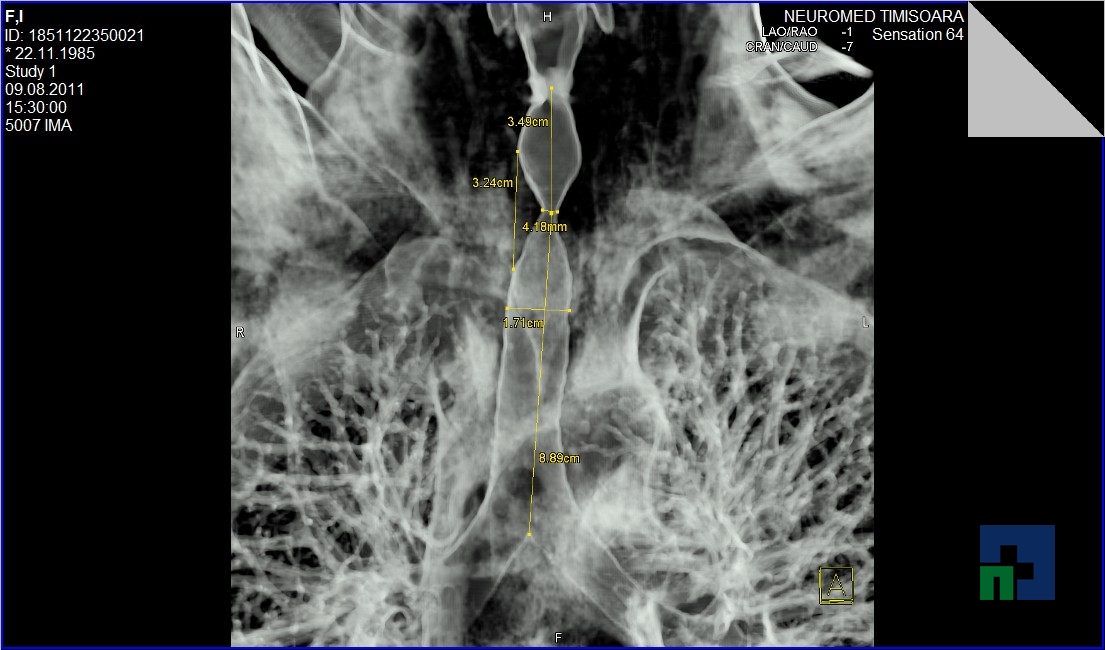

Examinare de rutină cerebrală, nativ și cu substanță de contrast (SDC) pentru diagnosticul:

- Accidentelor vasculare cerebrale ischemice sau hemoragice